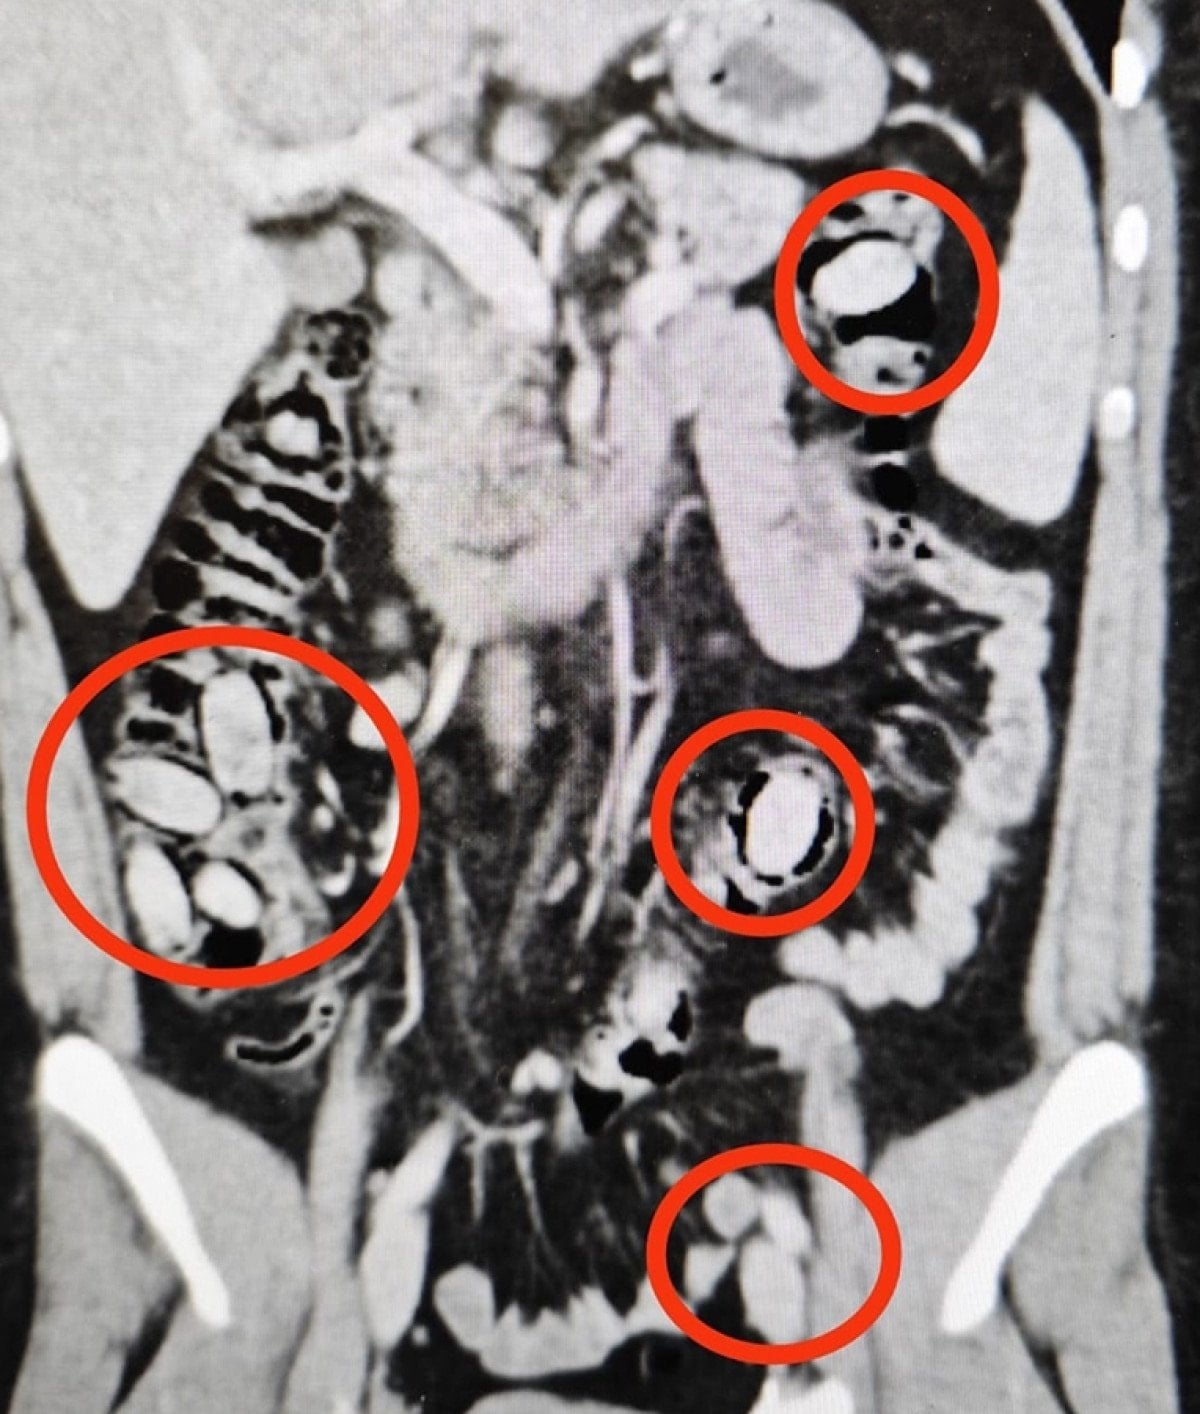

Hastane kontrolüne götürülen 25 yaşındaki S.A.’nın midesinde 44 kapsül sentetik uyuşturucu olduğu belirlendi.

Operasyonla midesindeki kapsüller çıkarılan S.A., hastanedeki tedavisinin ardından sevk edildiği adliyede çıkarıldığı hakimlikçe tutuklandı.